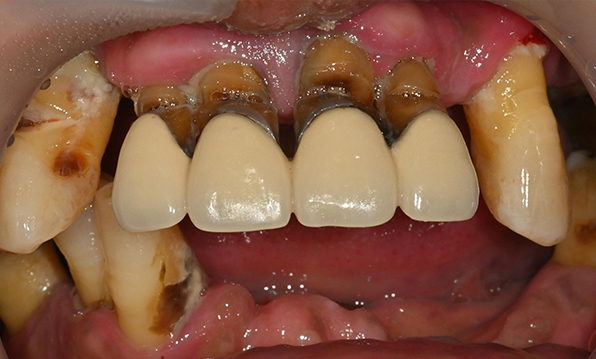

잇몸뼈가 얇은 상태

-

잇몸뼈 충분히 이식 후 임플란트 식립

성공을 위한 노하우, 잇몸뼈 재건 기술

전체 임플란트를 해야하는 환자들은

대부분 고령의 환자들로 오랜 틀니 사용

또는 노화로 인해 치조골이

거의 남아있지 않는 경우가 많습니다.

이 때, 치조골 이식을 병행하여 잇몸뼈 재건 후 안정적인 임플란트 식립을 하고 있습니다.

치료기간 : 2021.04.12~2021.09.15